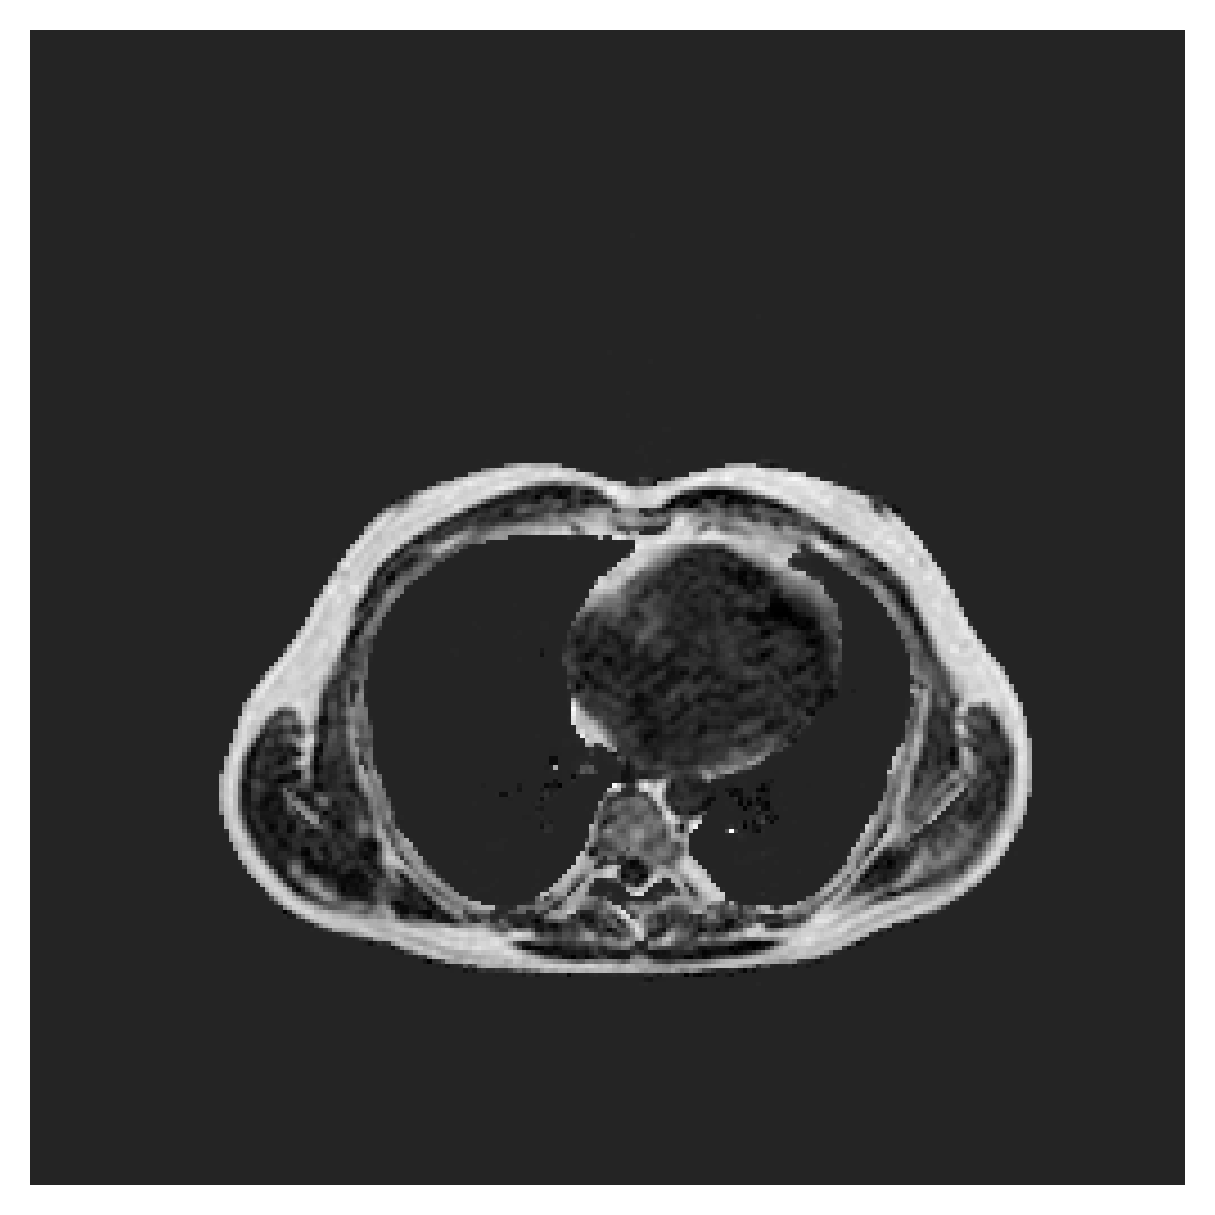

ACDC

([5]) The Automated Cardiac Diagnosis Challenge (ACDC) is a public benchmark multi-class heart segmentation dataset. It contains cine-MR images of 150 patients (of which 100 are available for training and the rest 50 comprise a test set), covering healthy scans and four types of pathologies in equal amounts, with annotations for the right ventricle (RV), myocardium (Myo) and left ventricle (LV) heart structures. We split the training set randomly, using 65 subjects for training, 10 for validation and 25 as a hold-out test set. Due to the large and varying interslice gap, we work with 2D slices instead of 3D volumes directly. This includes distance map computation.

We normalize the volumes and resize the slices to pixels. As the official dataset comes with full annotations, we create a synthetic point ground truth. This is done by first randomly choosing the centers of the point annotations within the class masks, followed by filling an ellipse with axes lengths of and (in pixels) around each center. The intersections of these elliptic discs with the underlying full annotations are then used as our point ground truth. See Figure 2 for an example of the created weak annotation mask. The point annotations are created for every slice, one for each foreground object present in the slice.